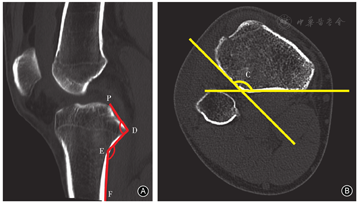

前期研究依据Kuwano等[10]报告的方法建立胫骨平台坐标体系,测量了上胫腓关节下方胫骨后外侧骨皮质长轴间夹角(∠C)、后外侧平台斜坡角(∠PDE)、后外侧斜坡骨干角(∠DEF)三项角度指标(图6)。我们根据这些数据设计了符合胫骨后外侧平台解剖形态的旋转支撑接骨板,获得了中国发明专利(中国专利号:CN104706413A)。